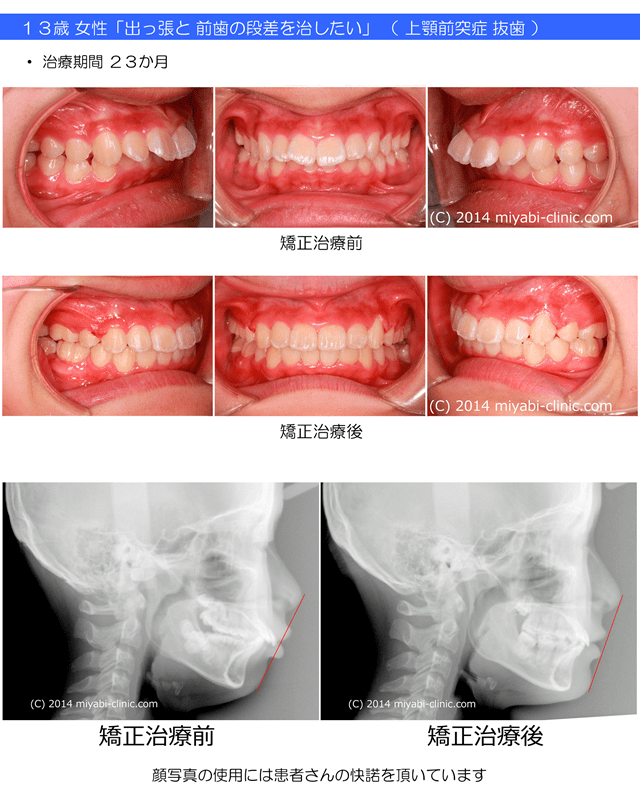

13歳 女性 捻転を伴う 上下顎前突症 治療期間22か月 唇側矯正装置(ホワイトワイヤー)を使用した上下顎第一小臼歯抜歯治療 参考治療費 約67万円(消費税込み73万円)(精密検査から終了まで) 矯正治療に伴う副作用の歯肉退縮、知覚過敏、失活、歯根吸収などは認められませんでした。